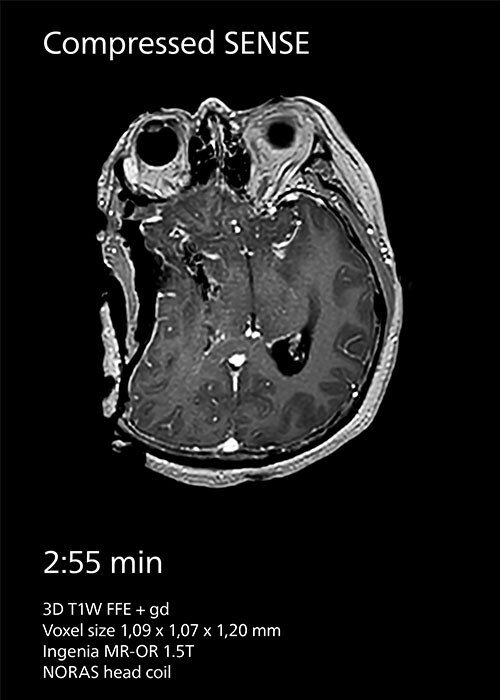

Because imaging speed in intraoperative MRI is important at Tokai, the center has been using SENSE parallel imaging since the beginning. In 2020, the team started employing Compressed SENSE instead to achieve greater scan time reductions. “At our hospital we prioritize speed and we have seen that Compressed SENSE helps us to reduce intraoperative MRI scan

time for our 3D T1W scans with about 40%.” Dr. Matsumae says.

Compressed SENSE reduces scan time from 3:59 min to 2:55 min with the same spatial resolution.